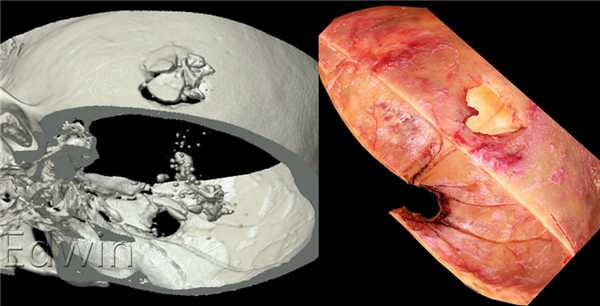

Огнестрельное повреждение головы оболочечной пулей.

Спавнение реконструкции на томограмме и нативном снимке со вскрытия. Видны выходной отверстие на наружной компактной пластинке и входное огнестрельное отверстие на внутренней компактной пластинке свода черепа.